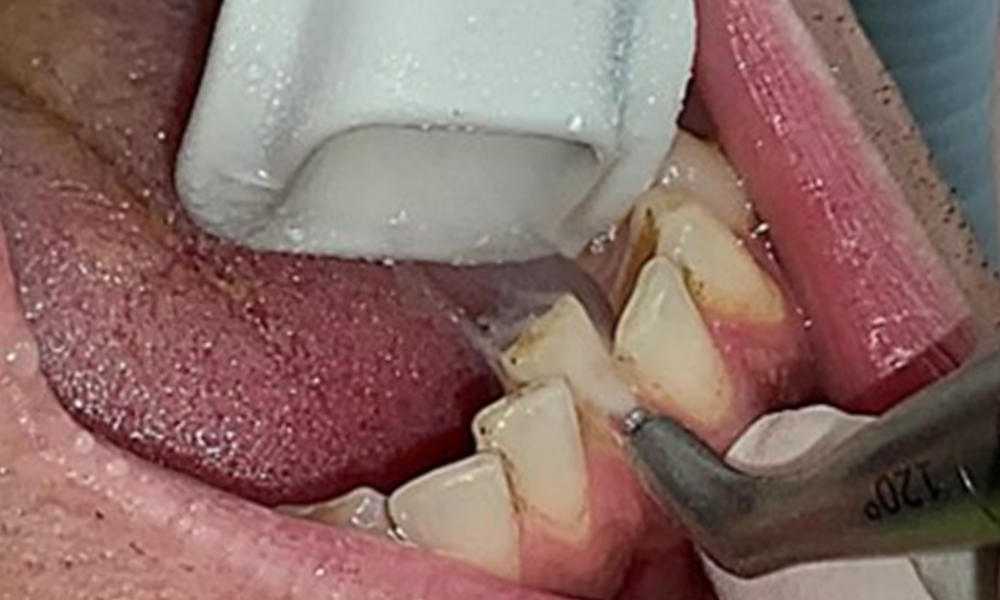

Instruction and motivation are important components of these appointments. Good home-based intraoral hygiene behaviour and understanding are important for patients. Plaque accumulation is particularly evident in the cervical regions (Fig. 8).

The arrows indicate plaque accumulations in the cervical region

Fig. 8: The arrows indicate plaque accumulations in the cervical region, © Dr R. Krapf

These must be discussed with the patient, and improvements to the teeth-brushing technique must be practised. A soft toothbrush attachment is recommended for home-based intraoral hygiene due to the presence of erosions and attritions.

It is also necessary to check that the interdental brushes – used by this patient on a daily basis – are the correct size and encourage consistent use (Fig. 9). Good intraoral hygiene minimizes the risk of periodontitis from smoking.

Use of the interdental brushes in the area near 44/45

Fig. 9: Use of the interdental brushes in the area near 44/45, © Dr R. Krapf